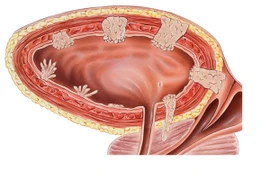

Bàng quang là bộ phận chứa nước tiểu nên dấu hiệu khi đi tiểu cũng có thể cảnh báo về bệnh ở bàng quang. Ung thư bàng quang điều trị ở giai đoạn sớm sẽ đem lại tiên lượng sống cao cho người bệnh.

Ung thư bàng quang không phải lúc nào cũng có một loạt dấu hiệu cảnh báo. Tiểu ra máu được coi là triệu chứng phổ biến nhất xảy ra ở 85% trường hợp mắc bệnh này.